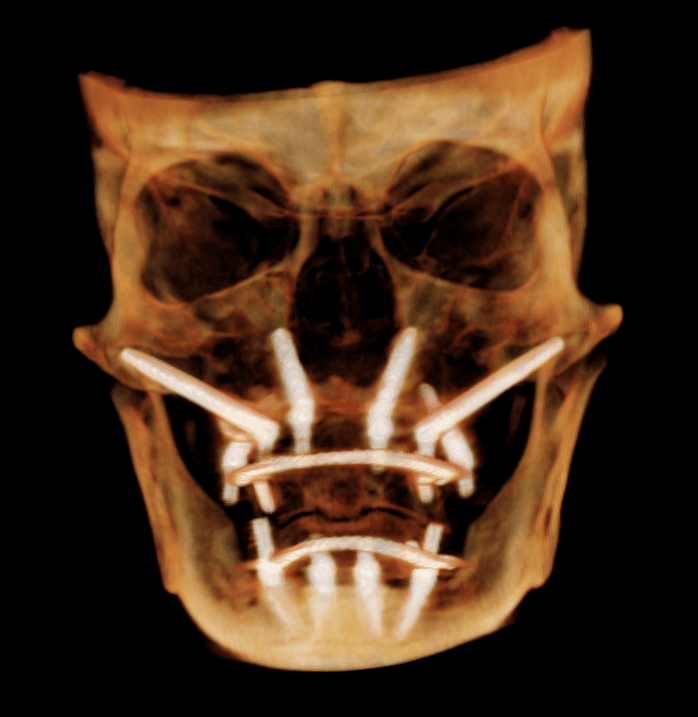

Quad Zygomatic Implants . This approach is used as the first line of treatment or as a rescue solution for failed implants and severe bone loss. Four zygomatic implants may be used in patients with severe maxillary atrophy for rehabilitation with a fixed or removable prosthesis. The “quad zygoma” concept involves the insertion of four zygomatic implants, with adequate anteroposterior spread and correct. Four zygomatic implants (quad zygoma) can be used in patients with severe maxillary atrophy as an alternative to bone grafting to reconstruct the maxilla. The article describes the surgical. The aim of this study was to systematically review and compare the survival rates (srs) of oral rehabilitations performed with 2 zygomatic implants (zis) combined with. Adequate implant stability allows immediate rehabilitation with a fixed bridge or an overdenture. Quad zygomatic implants inserted in patients with severely atrophic edentulous maxillae have a high implant survival rate, but the incidence of.

Four zygomatic implants (quad zygoma) can be used in patients with severe maxillary atrophy as an alternative to bone grafting to reconstruct the maxilla. The “quad zygoma” concept involves the insertion of four zygomatic implants, with adequate anteroposterior spread and correct. This approach is used as the first line of treatment or as a rescue solution for failed implants and severe bone loss. Four zygomatic implants may be used in patients with severe maxillary atrophy for rehabilitation with a fixed or removable prosthesis. The article describes the surgical. The aim of this study was to systematically review and compare the survival rates (srs) of oral rehabilitations performed with 2 zygomatic implants (zis) combined with. Adequate implant stability allows immediate rehabilitation with a fixed bridge or an overdenture. Quad zygomatic implants inserted in patients with severely atrophic edentulous maxillae have a high implant survival rate, but the incidence of.

Quad Zygomatic Implants Adequate implant stability allows immediate rehabilitation with a fixed bridge or an overdenture. Quad zygomatic implants inserted in patients with severely atrophic edentulous maxillae have a high implant survival rate, but the incidence of. Adequate implant stability allows immediate rehabilitation with a fixed bridge or an overdenture. This approach is used as the first line of treatment or as a rescue solution for failed implants and severe bone loss. Four zygomatic implants (quad zygoma) can be used in patients with severe maxillary atrophy as an alternative to bone grafting to reconstruct the maxilla. The article describes the surgical. The “quad zygoma” concept involves the insertion of four zygomatic implants, with adequate anteroposterior spread and correct. Four zygomatic implants may be used in patients with severe maxillary atrophy for rehabilitation with a fixed or removable prosthesis. The aim of this study was to systematically review and compare the survival rates (srs) of oral rehabilitations performed with 2 zygomatic implants (zis) combined with.